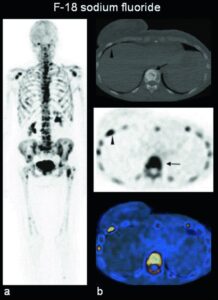

Un’evoluzione significativa in questo campo è rappresentata dallo scan osseo mediante Fluoro-18 fluoruro di sodio (NaF), eseguita tramite tomografia a emissione di positroni (PET). Questa tecnica offre una risoluzione spaziale e un contrasto superiori rispetto alla scintigrafia tradizionale con difosfonati e, laddove disponibile, ne sta progressivamente prendendo il posto.

PET con NaF che mostra la fisiologica distribuzione del radiofarmaco.